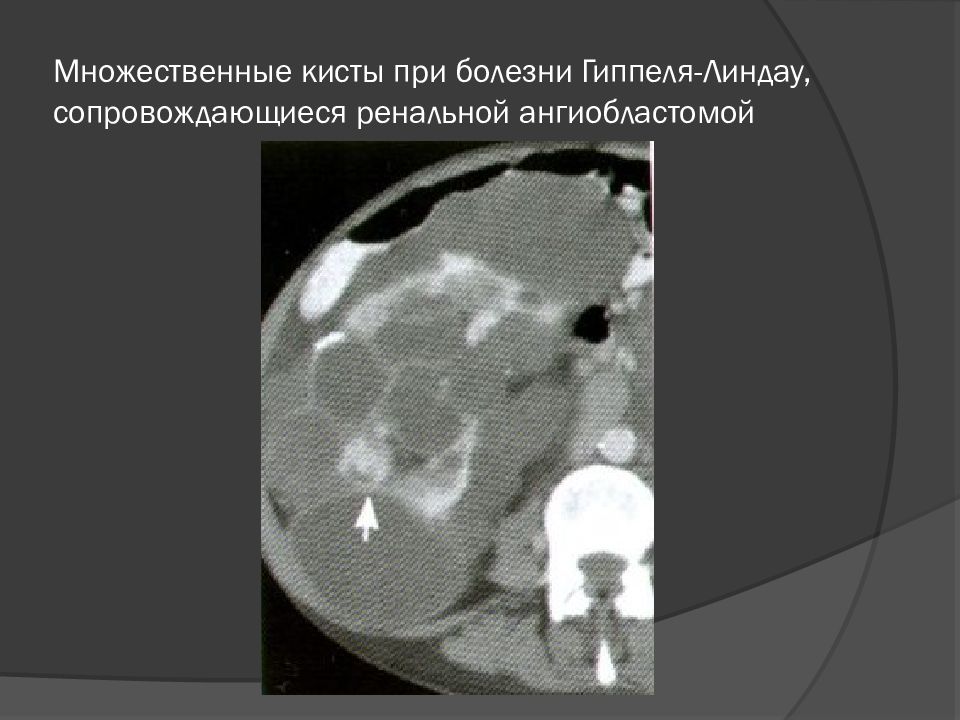

• Множественные кисты при болезни Гиппеля-Линдау, сопровождающиеся ренальной ангиобластомой

Слайд 29: Множественные кисты при болезни Гиппеля-Линдау, сопровождающиеся ренальной ангиобластомой